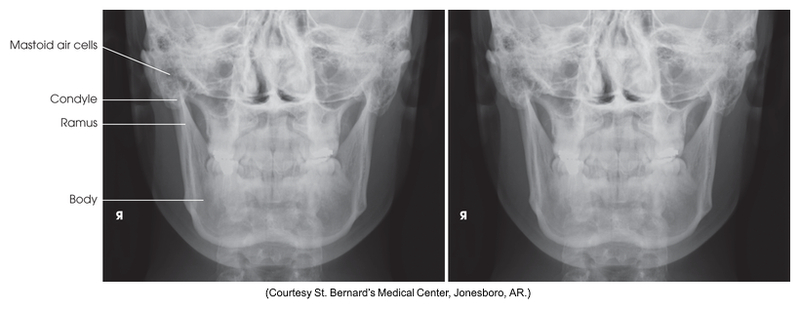

PA projection of mandibular rami

PA of mandibular rami